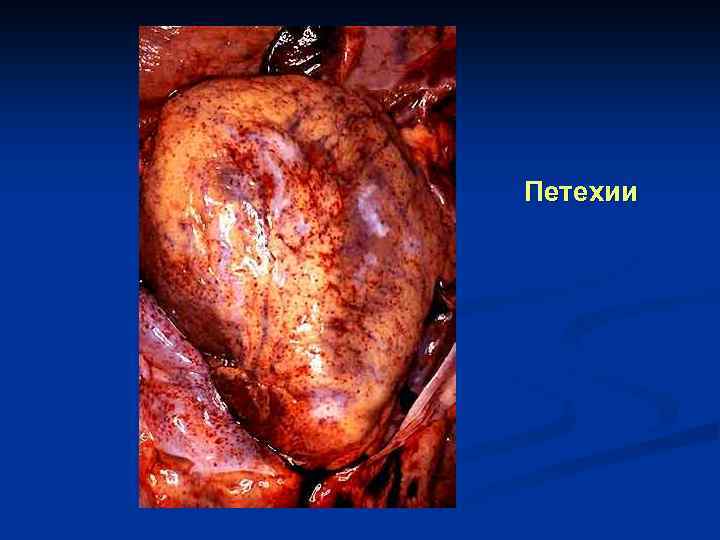

Петехии